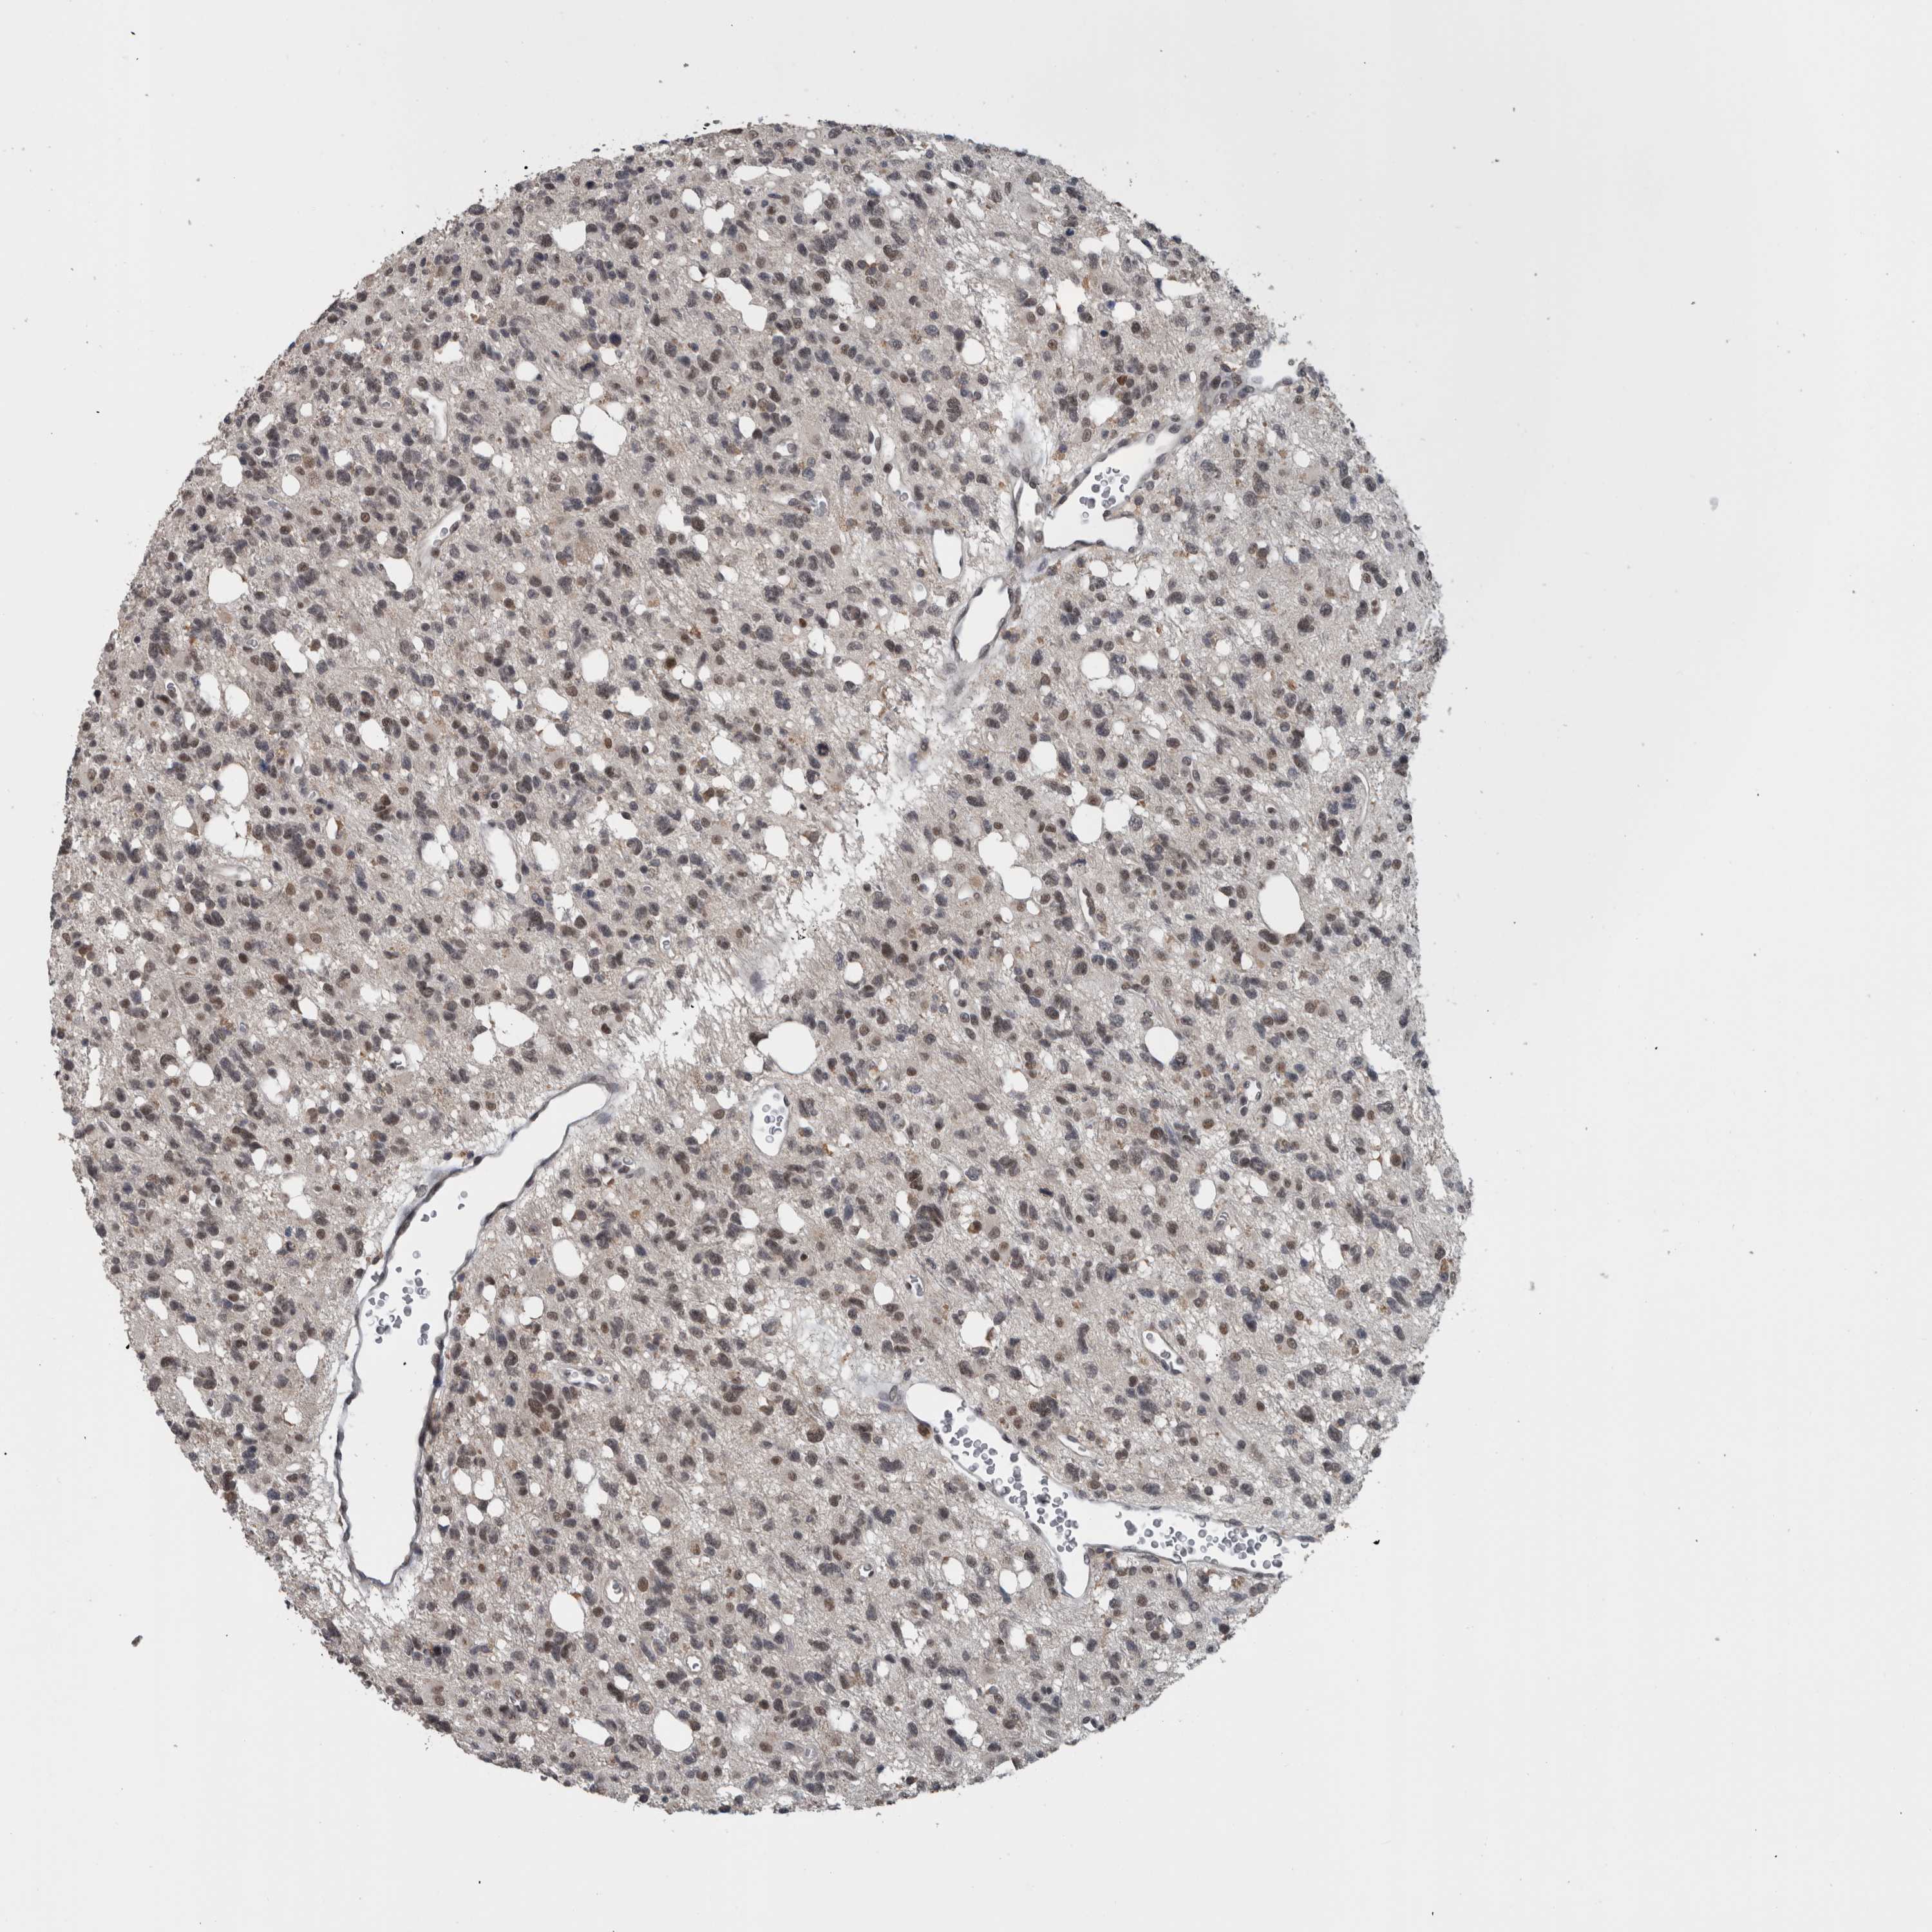

GLIOMA - Protein expressioni

A mouse-over function shows sample information and annotation data. Click on an image to view it in a full screen mode. Samples can be filtered based on level of antibody staining by selecting one or several of the following categories: high, medium, low and not detected. The assay and annotation is described here.

Note that samples used for immunohistochemistry by the Human Protein Atlas do not correspond to samples in the TCGA dataset.

Antibody stainingi

Antibody staining in the annotated cell types in the current human tissue is reported as not detected, low, medium, or high, based on conventional immunohistochemistry profiling in selected tissues. This score is based on the combination of the staining intensity and fraction of stained cells.

Each image is clickable and will lead to virtual microscopy that enables deeper exploration of all samples and also displays staining intensity scores, fraction scores and subcellular localization as well as patient and tissue information for each sample.

Antibody HPA024655

Staining

High

Medium

Low

Not detected

Intensity

Strong

Moderate

Weak

Negative

Quantity

>75%

75%-25%

<25%

None

Location

Nuclear

Cytoplasmic/membranous

Cytoplasmic/membranous,nuclear

Glioma, malignant, High grade

Glioma, malignant, Low grade